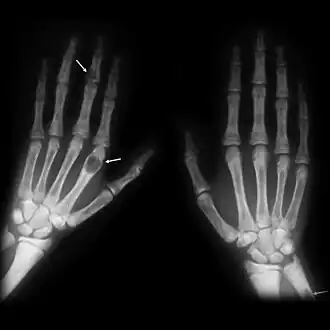

![]() Tumores pardos en las manos de un paciente con hiperparatiroidismo. | ||

Los tumores pardos son tumores del hueso que se producen como consecuencia de un exceso de actividad osteoclástica, como ocurre en el caso del hiperparatiroidismo. Consiste en tejido fibroso, hueso no laminar (hueso embrionario) y la vascularizción de soporte, pero no hay en ellos matriz ósea. En las radiografías se ven radiolucentes, apareciendo como lesiones líticas.

Su génesis es la siguiente: en enfermedades que, como el hiperparatidoidismo, se produce un exceso de actividad de los osteoclastos, éstos consumen el hueso trabecular que han depositado los osteoblastos. Aparecerán nuevos osteoblastos que fabricarán hueso nuevo y que, a su vez, será consumido. Este frente de formación-reabsorción ósea se expande, a veces más allá del contorno usual del hueso, afectando al periostio y causando dolor óseo.

Su característica coloración marrón se debe a la deposición de hemosiderina en las lesiones quísticas osteolíticas.